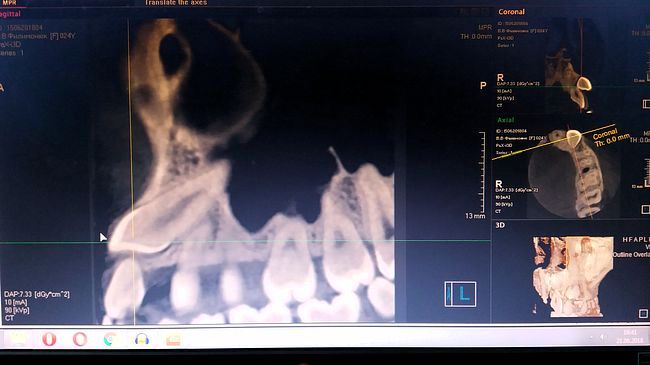

Так выглядит дистопия (неправильное положение ) зуба на снимке. Зуб не прорезался и занимает неправильное положение в кости.